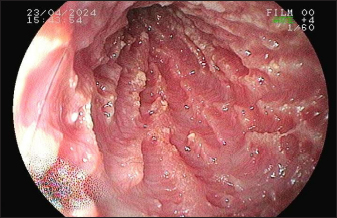

Given the lack of response to treatment and the test results, the patient was referred for an upper digestive endoscopy. The examination revealed a smooth esophagus with hyperemic cardia mucosa. The stomach had anatomical folds in the body region, and the mucosa had erythematous spots. The pylorus presented a hyperplastic appearance, while the duodenum exhibited edematous mucosa and an irregular surface caused by increased whitish content, which was suggestive of lacteal dilation and duodenitis (Fig. 4). Materials were collected from 15 fragments of the gastric and duodenal mucosa for subsequent histopathological analysis.

Fig. 4. Duodenoscopy of a dog with intestinal lymphangiectasia. Lacteal dilatation with a raised, whitish appearance in the duodenal mucosa.

Endoscopic evaluation by upper gastrointestinal endoscopy can reveal isolated, punctuated, or coalesced white spots related to dilation of the lymphatic vessels with or without the presence of rupture and extravasation of lymph (Jablonski, 2022). These findings were observed via duodenoscopy in this case, but it was not possible to determine whether lymphatic rupture was present. In addition, there was a correlation between the macroscopic findings and histopathology, which showed distortion of the crypts and lacteal dilatation. This correlation was also found in the literature (García-Sancho et al., 2011).